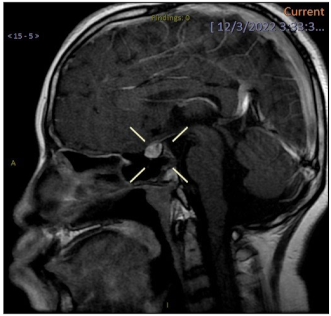

- O19. Prepubertal Vaginal Bleeding: A Retrospective Analysis of Prospectively Collected Data from a Tertiary Pediatric Gynecology Center in Greece

Introduction: Vaginal bleeding in prepubertal girls often elicits concerns from parents and health providers alike. The cause of bleeding can be as simple as vulvovaginitis or as devastating as sexual abuse or malignancy. It is important for all health providers to familiarize themselves with the differential diagnosis of prepubertal vaginal bleeding in order to utilize the appropriate medical examinations and reach a prompt diagnosis.

Aim: The aim of this study was to describe the clinical features of children with prepubertal bleeding and the appropriate medical investigations to reach a prompt diagnosis.

Methods: A retrospective review of prospectively collected data was performed. All children under the age of 10, who presented with vaginal bleeding, between January 2012 and December 2023, were included in the analysis.

Results: A total of 8 cases were retrieved with a mean age of 5.7 years (range 2–8 years). Detailed individual and family history was taken from all patients and complete clinical examination was performed. Vaginal swabs were taken, bone age was assessed and a pelvic ultrasound of internal genitalia was performed. In 2 cases pelvic and brain MRI were carried out to assist differential diagnosis. Hormone testing and especially LH-RH (Luteinizing Hormone Releasing Hormone) stimulation test were prescribed when necessary. Moreover, n 3 cases (37.5%) vaginoscopy was deemed necessary. Conclusively, 3 cases (37.5%) were diagnosed with precocious puberty, 1 case (12.5%) was diagnosed with genital hemangioma, 2 cases (25%) were diagnosed with vaginal foreign body, and in the 2 remaining cases (25%) no diagnosis was reached and thus were assigned to a monitoring schedule.

Conclusions: Vaginal bleeding in prepubertal girls is a complex differential diagnosis problem that needs a holistic approach to investigate all possible causes. The cooperation between specialties is paramount to ensure the optimal handling of these incidents.